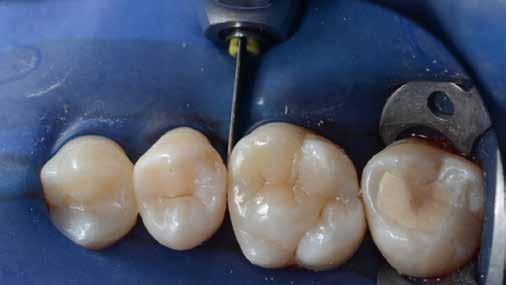

A posterior fogak direkt kompozit restaurációja az egyik leggyakrabban végzett beavatkozás a fogászatban. Az elmúlt években kiemelt figyelem irányult az elérhető eredmények optimalizálására, különös tekintettel a II. osztályú kavitás dobozának (Class II box) kialakítására, és a polimerizációs zsugorodásból eredő feszültség kezelésére. A téma körüli széles körű szakmai diskurzus ellenére van egy olyan lépés, amely gyakran nem kapja meg a kellő figyelmet: a mechanikai formázás protokollja. A mechanikai formázás alatt a restauráció kontúrjának kialakítását, a felesleges kompozit eltávolítását értjük a marginális szélekről, illetve ide tartozik a végső polírozás is. Ez a folyamat három fő lépésre bontható: a felszín oxigén által gátolt, nem polimerizált rétegének eltávolítása, a durva finírozás és a végső polírozás. Jelen publikációban részletesen bemutatjuk ezeket a lépéseket, valamint egy klinikailag hatékony megközelítést vázolunk fel a direkt posterior kompozit restaurációk befejezésére.

végső polírozása

A végső polírozás célja egy sima, „zománcszerű” felszín kialakítása, amely a páciens lágyrészei számára komfortos, esztétikailag kedvező, valamint ellenáll a lerakódásoknak és az elszíneződésnek. Ez a folyamat négy fázisból áll.

1. fázis

Finom és szuperfinom, közepes méretű polírozó korongok alkalmazásával 10 000–15 000 fordulat/perc sebességen történik a restauráció peremének polírozása. A korongokat hátrafelé irányuló mozdulatokkal, 45°-os szögben kell vezetni a fog hossztengelyéhez képest.

(Fontos: ne váltsunk szuperfinom korongra addig, amíg a finom koronggal el nem távolítottunk minden látható karcolást a tömés felszínéről!)

2. fázis

Finom, gyémánttal impregnált szilikon polírozófejet használunk vízhűtéssel a restaurátum széleinek és a csücsök-lejtők polírozására. Ez a lépés fokozza a restauráció fényét, a karcolások már a durva finírozási szakaszban el lettek távolítva.

3. fázis

Kecskeszőr kefét (pl. Shiny S, https://optident. co.uk/product/shiny-s-goat-hair-brushes/) célszerű alkalmazni stabil nyomással, vízhűtés nélkül, a restaurátum barázdarendszerének polírozására. A polírkefe pumisz pasztával (pl. Vertex® Pumice Plus, https://www.dentaltotal.es/images/ marcas-dentaltotal/VERTEX/CATALOGO_VERTEX.pdf) használandó. Ez a lépés kiküszöböli a barázdákban maradó karcolásokat, amelyek középtávon hajlamosak elszíneződni.

4. fázis

A végső fényesség az 1 mikron szemcseméretű, alumínium-oxid alapú, vízbázisú polírozópasztával (pl. Enamelize®, Cosmedent; https://www.cosmedent.com/product-category/finishing-and-polishing/) érhető el, valamint filc polírozófejek és korongok segítségével. A polírozás fokozatosan

növekvő fordulatszámmal (3000–20 000 fordulat/perc) és csökkenő nyomással történik. A pasztát mindig a fogra/restaurációra kell felvinni, nem pedig a korongra, így elkerülhető a paszta szétszóródása a kezelőben. (Lásd a 10. és 11. ábrát.)

Ezt követően a fogat puszter használatával letisztítjuk, majd a pácienst elbocsátjuk.

Amint látható, ez a protokoll egyszerű és kiszámítható módszert kínál az I. és II. osztályú direkt posterior kompozit restaurátumok tartós, esztétikus felszínének kialakítására (/spear-review/2013/08/evaluating-facial-esthetics-facial-profile).